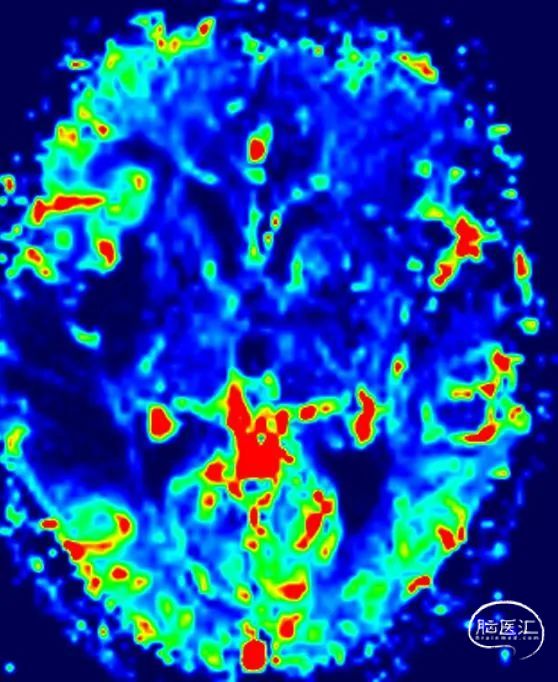

MR灌注

TPP